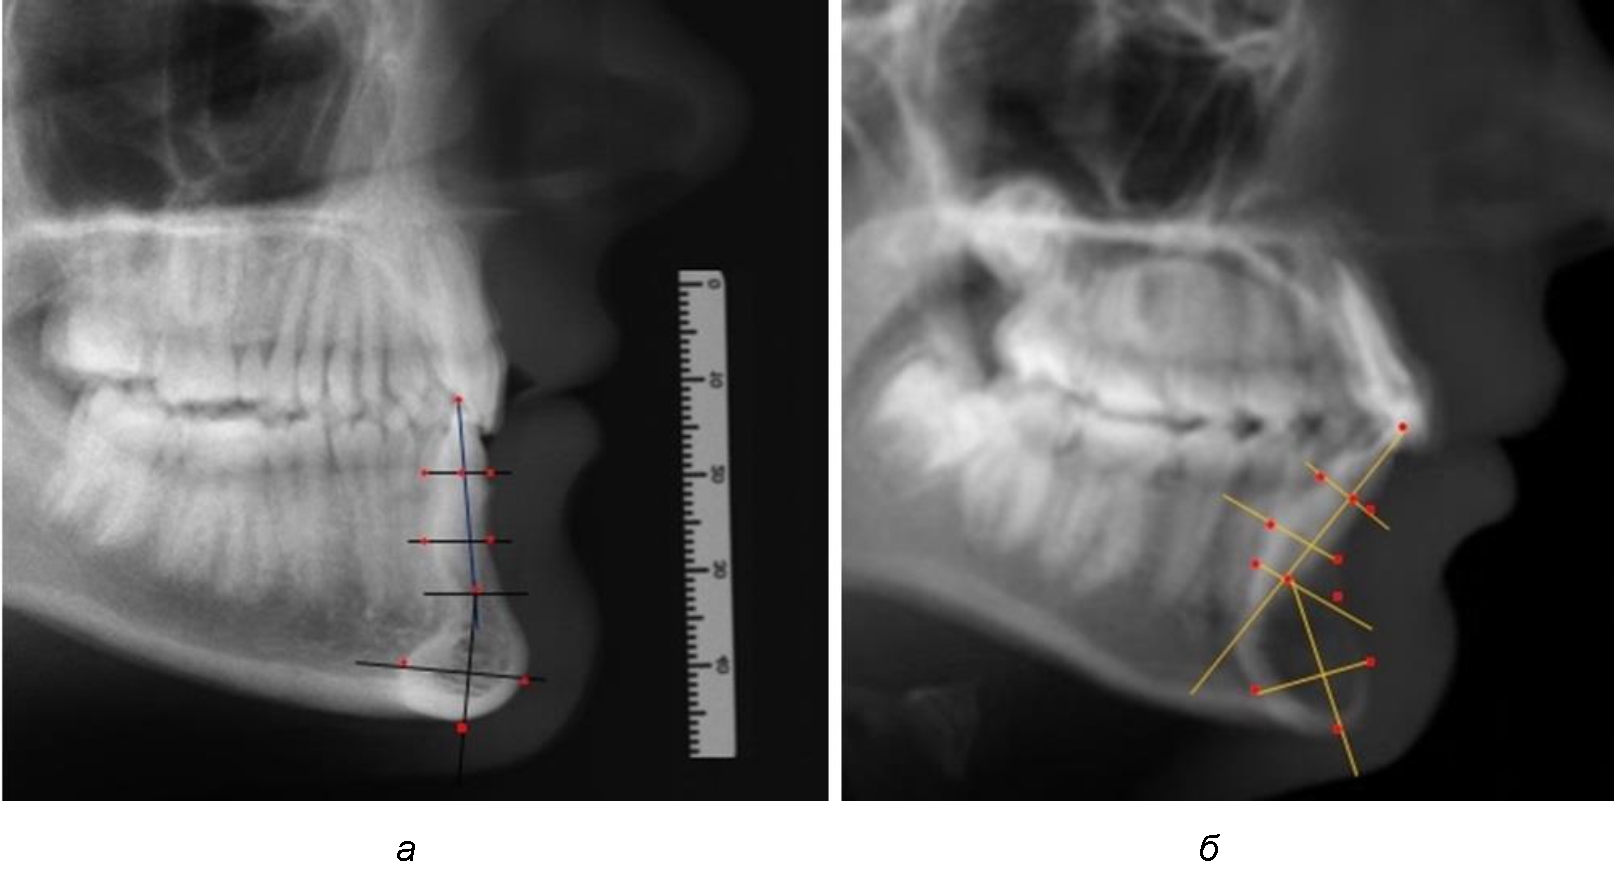

Нередко отмечается деформация подбородочного выступа и различное его положение по отношению к зубоальвеолярной части сегмента. При мезиальной окклюзии нередко нижняя подбородочная точка смещается кзади по отношению к условной срединной вертикали нижнего резца, а при дистальной окклюзии отмечается компенсаторное отклонение подбородка кпереди (рис. 5).

Рис. 5. Особенности нижнечелюстного резцового сегмента на ТРГ у людей при мезиальной (а) и дистальной (б) окклюзии

Кроме того, так же как и у людей с физиологической окклюзией, определялось различие в положении апикальных точек Downs и Schwarz, что, по нашему мнению, может определять тактику лечения патологических форм протрузии/ретрузии резцов с учетом биотипа костной ткани.